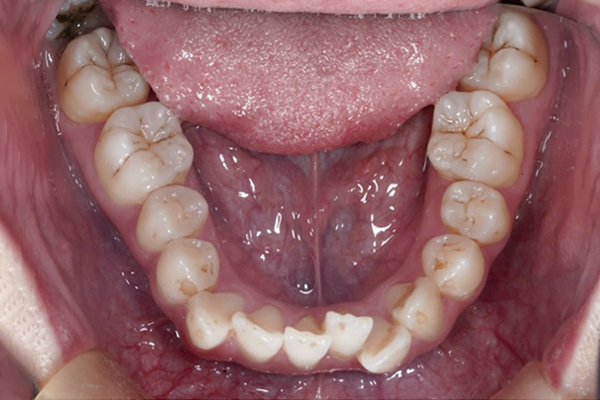

BEFORE

• ずっと叢生(ガタガタ)が気になっていた。

【3ヶ月経過の変化】

• 前歯の重なりが減り、アーチが広がってきました。

• 下の歯はほとんど並びました。